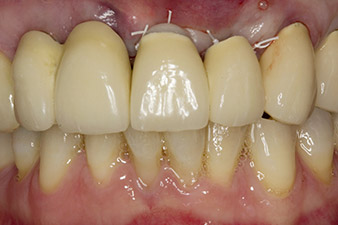

When the patient first presented, teeth 21, 22 and 23 had been restored with splinted crowns, now 19 years old, which were bonded to the implants at positions 12/11 by an attachment (cf. Fig. 2).

The x-ray revealed horizontal bone loss around teeth 21 and 22 (Fig. 1). When the crown block was removed, these teeth were unintentionally extracted with it.

Tooth 23 displayed a horizontal-coronal fracture and was restored with a post and core build-up for the temporary restoration. The plan was to place a zirconium oxide bridge on the existing implants at positions 12 and 11 and to place two new implants at positions 22 and 23.